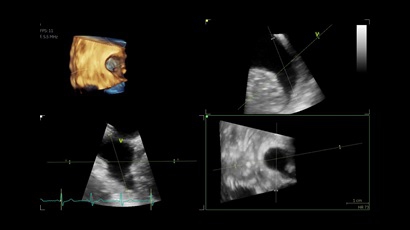

• Vivid IQ 4D с поддержкой технологии объемной реконструкции

4D:

Да

• Режимы: 4D, 2D (B-режим), цветной допплеровский режим, режим энергетического допплера, M-режим, цветной M-режим, спектральные режимы импульсно-волнового допплера (PW) и непрерывно-волнового допплера (CW), визуализация скорости движения тканей.

• 4D AUTO AVQ - модуль автоматического выравнивания, сегментации и обсчета размеров кольца аортального клапана по объемным данным.

• 4D AUTO LVQ - модуль расчета массы миокарда ЛЖ на основе данных 4D-исследования.